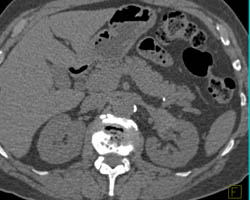

CASE NUMBER 3,554

Renal Artery Aneurysm